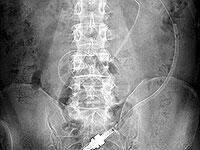

写真1は 70 歳、男性、糖尿病で慢性心不全の患者ですが、直腸に便塊がありカテーテルが持ち上げられ排液されませんでしたが、浣腸して注排液がスムースになりました。

55 歳、男性、糖尿病の患者で1月 26 日に導入後の写真です。

2004 年5月9日、カテーテル先端は左腸骨

2004 年5月 25 日、カテーテル先端は臍部

2004 年6月 17 日、カテーテル先端は左腸骨

2004 年7月8日、カテーテル先端は右上腹部

2004 年8月3日、カテーテル先端は左腸骨